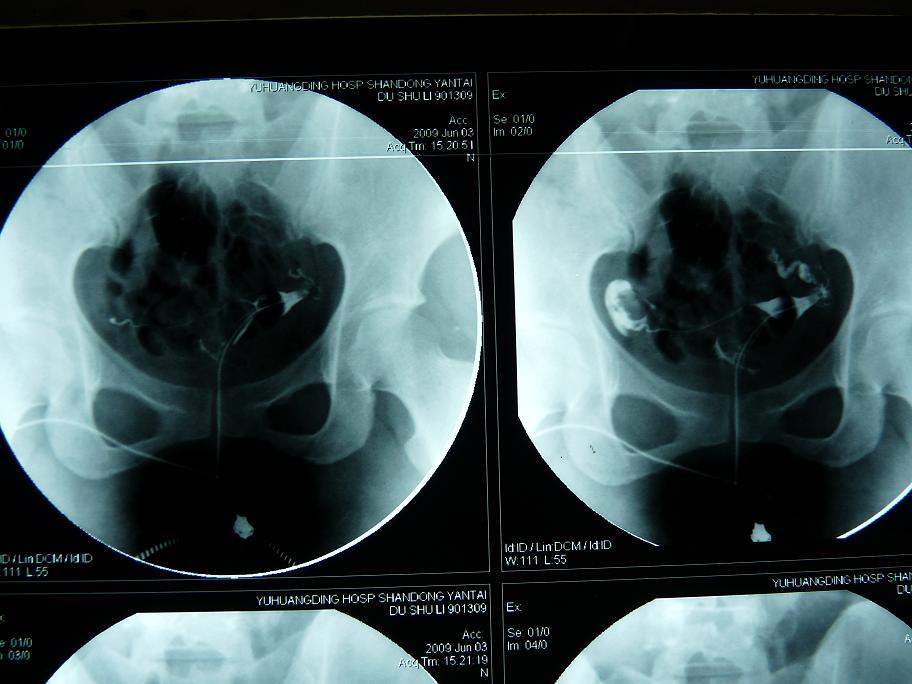

以下是引用黑白光影在2009-6-6 9:58:00的发言:[br]左侧输卵管粗细不均、僵硬、通而不畅,右侧输卵积水。